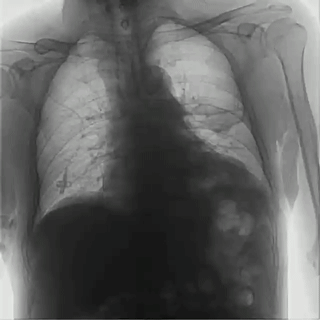

普利德多功能動(dòng)態(tài)DR采用100μm動(dòng)態(tài)平板探測(cè)器,實(shí)現(xiàn)5.0lp/mm超高分辨率成像,大幅提升細(xì)節(jié)檢測(cè)能力;動(dòng)態(tài)檢查幀率高達(dá)30幀/秒,有效避免漏診、誤診;靜態(tài)攝影有效像素高達(dá)1800萬(wàn),較之于傳統(tǒng)900萬(wàn)點(diǎn)片像素,圖像細(xì)節(jié)更加清晰細(xì)膩,有助于醫(yī)生準(zhǔn)確判斷病灶的位置、形態(tài)和大小,為急診救治提供可靠依據(jù)。